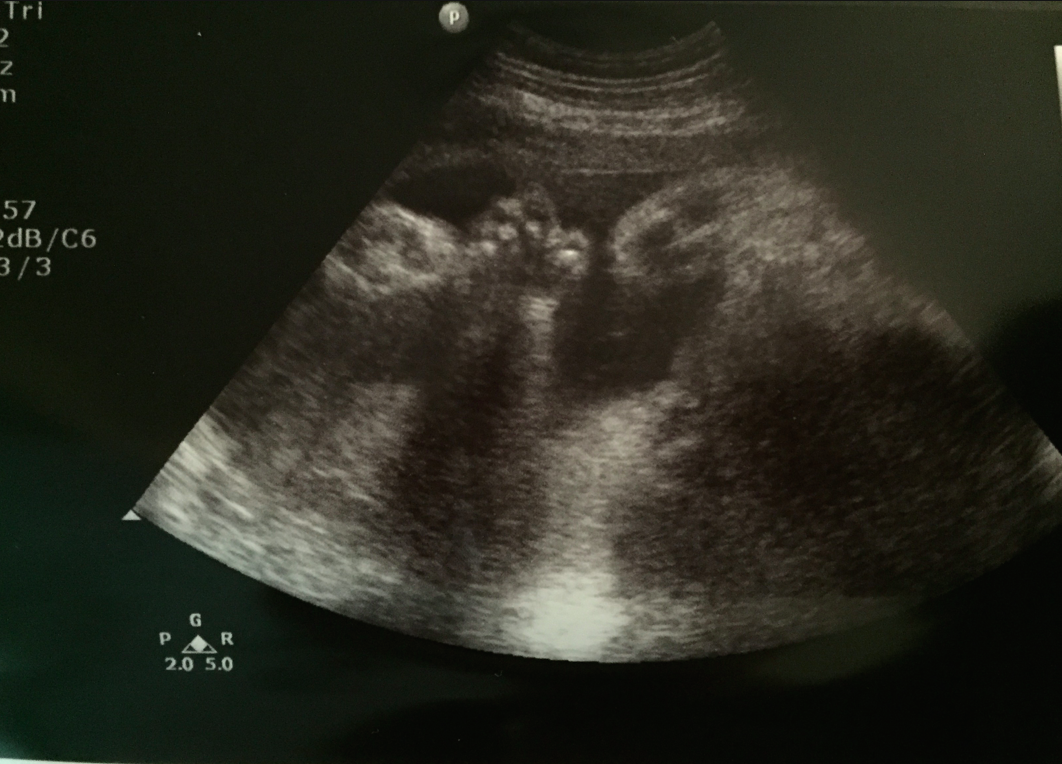

除咗度BB呱嘅「三圍」睇下生長之外,我哋都一齊由頭睇到腳一次~見唔見到虎爪拳?不過今次最impressive嘅係睇佢嘅樣貌~S醫生locate咗兩個眼框、鼻骨俾我哋睇,推後少少就係嘴仔了,佢話BB呱個嘴唇厚啲喎﹗哈哈~唔係孖潤腸吧?﹗希望係同我一樣嘅熱情厚嘴唇啦~(原來似媽媽個樣⋯暗笑中~)原來平時睇個嘴嘴係兩條幼線,但BB呱個嘴係兩條粗線,大概就係鉛筆同蠟筆畫出嚟嘅分別吧?